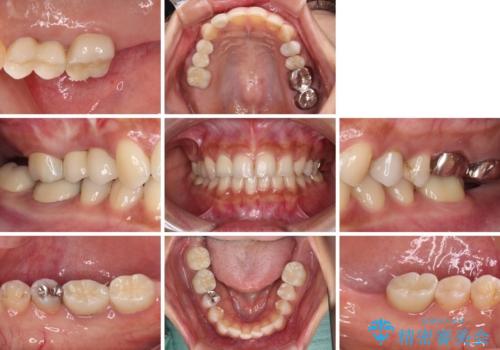

- 冷たいものがしみたり、ものが挟まったり、噛んだときに痛んだりするとのことで来院された患者様です。

レントゲン写真などで診査した結果、奥歯の銀歯の下にはむし歯が多く存在し、右上の奥歯は歯根が破折していました。

破折した歯を抜去し、インプラントによる補綴を行うこととしました。

銀歯の下のむし歯については、優先度の高い方からセラミッククラウンなどで治療していくこととしました。

治療開始時は右上奥歯と前歯のみが気になっていたのですが、その後下顎左右の奥歯に強い痛みや銀歯の脱離などが頻発し、問題のあるところは全て治療を行うこととしました。